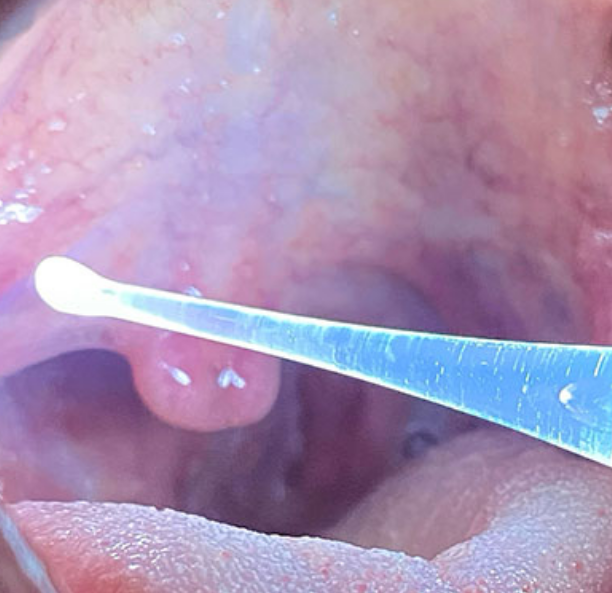

편도결석 제거기

편도결석 빼는 법 중에서 수술적인 치료를 제외하고 가장 효과적인 것은 편도결석 제거기 또는 흡입기를 사용하는 방법입니다. 온라인이나 오프라인에서 쉽게 구입이 가능한 편도결석 제거기는 온라인에서 11만 원 내외로 구입이 가능합니다. 또한 이비인후과에서 편도결석 제거기를 이용하여 치료도 가능하니 병원을 방문하여 제거를 하는 것도 좋은 방법입니다.

구입을 하고자 한다면 장단점을 잘 따져보신 후에 편도결석 제거기를 구입하는 것이 좋을 것으로 생각됩니다..